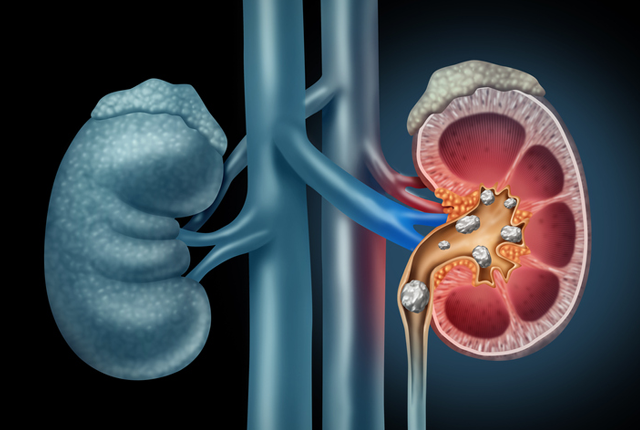

4. kép:

Vesekő sematikus ábra

A képen a vesekövek láthatóak mind a vesemedencében és annak kehelyvégeiben valamint a húgyvezeték kezdeti szakaszán. Az ábra jól szemlélteti, hogy az ilyen kövek hogyan zárhatják el a vizelet útját és okoznak ezzel vizeletelfolyási akadályt.